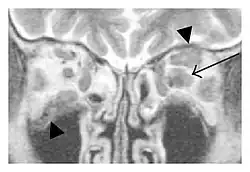

The extent of inflammation that can occur in IgG4-ROD is well demonstrated on magnetic resonance imaging (MRI).

Infraorbital nerve enlargement (IONE) is considered to be a particularly suspicious sign of IgG4-ROD, but seems to occur only when inflammation is in direct contact with the infraorbital canal.[10] IONE is defined as the infraorbital nerve diameter being greater than the optic nerve diameter in the coronal plane.